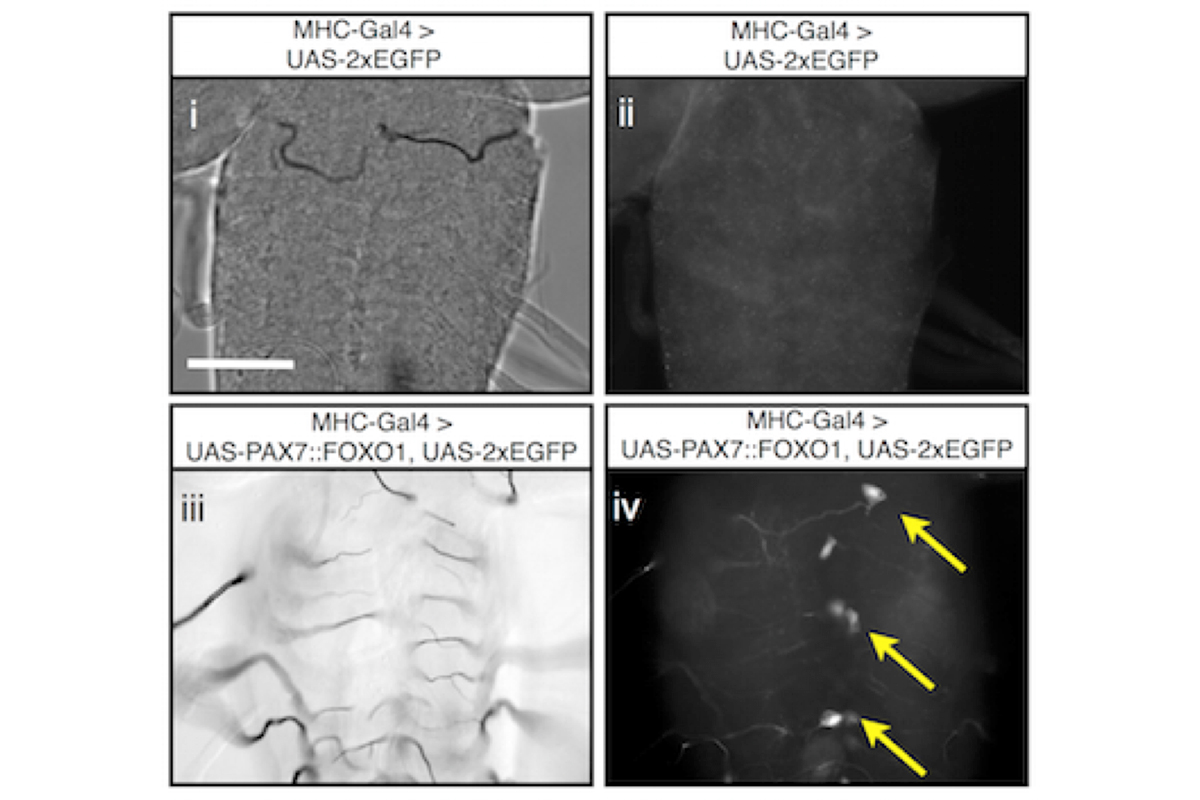

Figure 1: Expression of human PAX7::FOXO1A oncoprotein in Drosophila muscle leads to metastatic cells that populate the Central Nervous system. — Magnified view of the central nerve cord of a 3rd instar larva, top panel control, bottom panel PAX7::FOXO1A positive. i & iii) brightfield image, ii & iv) GFP fluorescence. Note the GFP positive, neoplastic cells that invaded the central nerve cord (arrows).

ARMS uniquely associates with chromosomal translocations t(2;13)(q35;q14) and t(1;13)(p36;q14), leading to the production of the fusion oncoproteins PAX3::FOXO1A or PAX7::FOXO1A. Expression of a human PAX7::FOXO1A fusion protein alone in Drosophila mesoderm leads to a population of free larval myoblasts that transform into aggressive cells that leave the muscle compartment, migrate, and invade nonadjacent tissues, including the central nervous system (CNS).

This cellular behavior is reminiscent of metastatic disease in which transformed cells invade and integrate into adjacent tissues. We are studying this Drosophila ARMS model to better understand metastatic behaviors. A screen for new therapeutics to treat this disease is underway. We are currently translating our screen positives to human cancer cells and mouse xenograft studies.